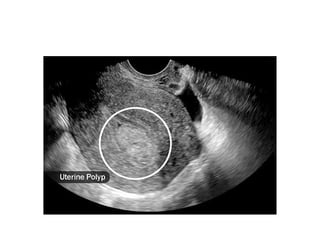

Endometrial polyps

●Localized overgrowth tissue, containing glands,

stroma, and blood vessels, covered with

epithelium

●Stimulated by estrogen

●Diagnosed by visualization and removal by

hysteroscopy

●Send for HPE to exclude malignancy

Endometrial polyps ●Localized overgrowthtissue, containing glands, stroma, and blood vessels, covered with epithelium ●Stimulated by estrogen ●Diagnosed by visualization and removal by hysteroscopy ●Send for HPE to exclude malignancy